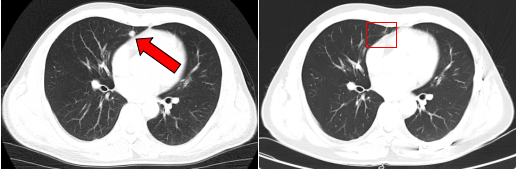

治疗前后鼻咽部病灶、咽后淋巴结病灶对比( 左:治疗前,右:治疗后)

治疗前后的肺部转移病灶图像对比( 左:治疗前,右:治疗后)